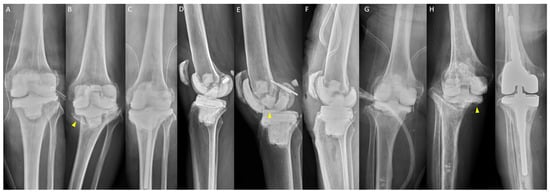

2.4. Postoperative Protocol

Radiographic evaluations, including knee weight-bearing anteroposterior, lateral, and Merchant views, and lower-limb scanogram, were conducted 1 week after RA (Figure 1). Radiographs were obtained monthly before reimplantation or when the patient experienced knee pain, swelling, instability, or deformity. Rehabilitation was partial weight-bearing with crutches without a hinged brace. Each patient received at least 4 weeks of organism-specific intravenous antibiotics according to the recommendations of an infection consultant. Oral antibiotics were maintained until C-reactive protein levels and erythrocyte sedimentation rates decreased.

Figure 1. Radiographs of the articulating spacer obtained 1 week after resection arthroplasty: (A) standing anteroposterior view; (B) standing lateral view; (C) merchant view; and (D) scanogram of the lower limb.